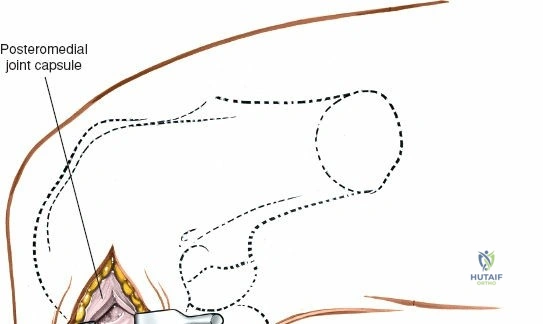

Open Medial Meniscectomy – The Specific Approach

The open medial meniscectomy, once the standard, is now reserved for scenarios where arthroscopy is unavailable, technically infeasible (e.g., severe arthrofibrosis, large foreign bodies, or specific revision surgeries), or for very large, difficult-to-manage loose bodies. The seed content heavily focuses on this approach.

Dissection:

- Joint Capsule: The approach typically involves either a medial parapatellar arthrotomy, splitting the fibers of the vastus medialis obliquus (VMO) longitudinally, or a direct incision of the medial capsule over the joint line, medial to the patellar tendon. For direct access to the medial meniscus, a paramedial capsular incision along the medial border of the patella and extending distally can be made.

Exposure of the Meniscus:

- Retractors are carefully placed to expose the medial tibiofemoral compartment. Self-retaining retractors may be used, but care must be taken to protect the articular cartilage.

- To improve visualization, the knee is brought into hyperflexion (as per seed content, "beyond a right angle"). This maneuver, combined with external rotation of the tibia and a valgus stress applied to the knee, widens the medial compartment. This allows for improved access to the posterior horn of the medial meniscus.

Closure:

- Carefully repair the joint capsule and deep fascia using absorbable sutures. This helps restore joint stability and minimize synovial fluid leakage.